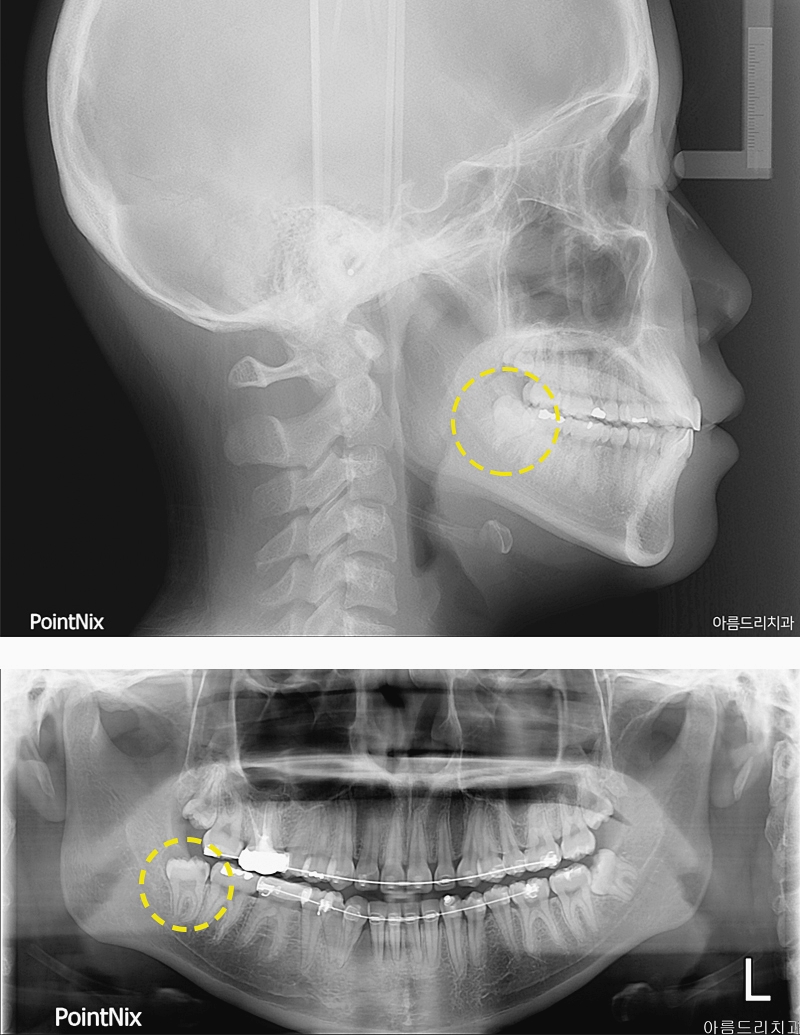

사랑니의 발치 여부를 이야기할 때 빼놓을 수 없는 부분이 매복사랑니일텐데요. 이름 그대로 잇몸 밖으로 사랑니가 모두 나오지 못하였을 때 부르는 말이었었어요. 옆으로 누워 있어 근처에 있는 어금니의 머리나 뿌리 부분에 결려 머리만 치아가 자란다던가 전부 잇몸 속에 숨어 있는 경우도 있을 수 있었어요. 일부만 자란 경우 사이에 음식물이 끼기도 하고 제거가 어려워 치태가 쌓이기 쉽기 때문에 구취가 발생하기도 하며 충치로 인한 매복사랑니통증이 동반되기도 하는 것이에요. 밖으로 올바르게 맹출 된 사랑니는 제 3대구치로 어금니의 역할로 사용할 수 있겠지만 똑바르니 못하거나 자라지 못한 경우 관리의 문제, 충치, 주변 다른 치아의 배열을 망칠 수 있기에 매복사랑니후기를 권해드리고 있었었어요. 식습관 변화로 인해 턱관절이 좁아지고 있다고 하는데요. 그러한 이유로 사랑니가 자랄 공간은 더욱 부족해지고 이로 인해 매복사랑니가 되는 사례들도 증가하고 있었었어요. 매복사랑니라고 다 같은 것이 아니라 종류가 있고 어떠한 종류인가에 따라 발치하는 과정도 달라지기에 이에 대해 알아두시는 것도 도움이 되실거에요. 어떤 기준을 통해 보느냐에 따라 종류를 나누는 방법도 달라지는데요. 먼저 매복 각도에 따라 구분을 하기도 해요. 수평 매복 사랑니는 앞 치아와 90도의 각도로 매복된 치아를 말하는 것이에요. 수평으로 누워 있어 자라면서 앞 쪽의 어금니를 밀기 때문에 치열의 흐트러짐이 나타날 수 있고 매복사랑니통증도 일반 사랑니보다 심하게 나타나는 편일 수 있었었어요. 수직은 앞 치아와 평행한 상태로 매복된 것을 의미해요. 원심 경사 매복이란 것도 있는데 이는 치아의 머리 부분이 뒤로 향해 있는 경우를 말하는 것이에요.

매복 정도에 의해 구분을 할 수 있는데 이는 매복사랑니발치후기 과정에 았어서도 차이점을 보이고 있었었어요. 단순 매복의 경우 치관부가 뼈에 덮이지 않고 잇몸으로만 덮혀있는 케이스를 의미해요. 치료 과정 또한 잇몸 일부를 절개한 후 발치를 진행하면 되기에 일반적인 사랑치 발치와 비슷하게 비교적 쉬운 종류의 매복치라 할 수 있었어요. 복잡 매복의 경우에는 치관부가 잇몸이 아닌 뼈에 의해서 덮혀인는걸 의미하는데요. 기울어져 있거나 치조골 안 3분의 1정도가 매복되어 있는 경우에요. 복잡 매복사랑니발치후기 과정에선 잇몸 절개는 물론 치아 분리술이라는 치아를 잘게 조각 내어 분리하는 과정을 동반해야 했었었어요. 다음의 경우는 완전 매복이에요. 완전 매복은 치관부 전체가 완전히 뼈에 묻어 있는 케이스를 말하는 것이에요. 이는 치조골을 일부 삭제하는 것과 함께 잇몸 절개, 치아 분리술 등 복합적인 여러 시술이 이루어져 발치 과정을 진행하기에 고난이도의 시술이기도 하며 이에 맞는 의료진의 실력과 기술이 필요로 하겠어요. 매복사랑니는 턱 뼈 안에 낭종을 만드는 경우가 생기기도 하여 빠른 발치를 하는 것이 중요한데요. 종류에 따라 치료 과정이 다르기에 안전한 발치를 위해서는 병원 선택에 있어 여러 부분을 고려해야 하겠어요. 말 그대로 숨어있는 치아이기에 관련 검진을 정확히 할 수 있는 장비의 보유 여부는 물론 복잡한 여러 과정을 동반한 발치를 진행할 수 있기에 경험과 실력이 풍부한 의료진을 살펴보는 것이 중요한 부분이겠어요.